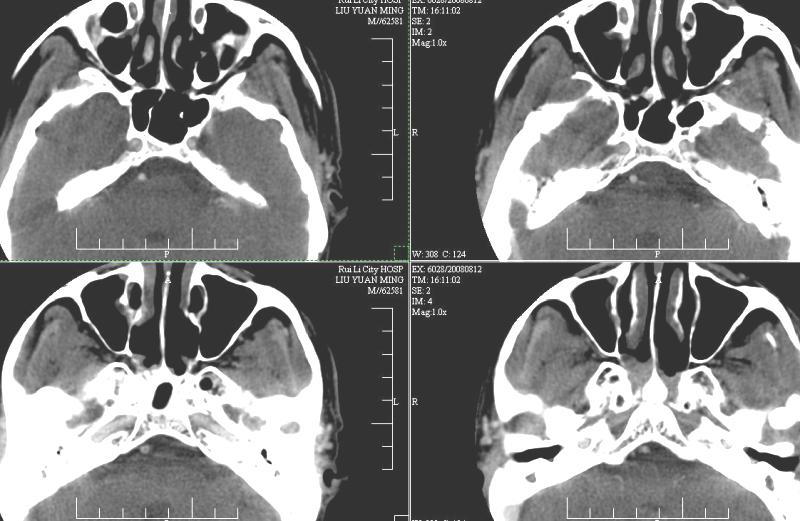

以下是引用zsl6918在2008-8-12 22:23:00的发言:[br]还是首先考虑鼻咽癌。

以下是引用ydx_74在2008-8-12 22:09:00的发言:[br]不考虑鼻咽癌。没有淋巴结肿大,没有颅底骨质破坏,咽隐窝、咽鼓管咽口存在,咽旁间隙清楚,平扫ct值34hu,增强动脉期81hu,实质期约85hu,增强幅度达50多,除外增强时机没有掌握好因素,可以考虑鼻咽纤维血管瘤吗?

以下是引用卜一在2008-8-13 8:07:00的发言:[br][br] 鼻咽部新生物,性质待定(不排除鼻咽癌可能);建议行鼻咽镜检查(活检)。 [br]支持!

以下是引用xulianj在2008-8-12 21:30:00的发言:[br]建议活检!结节病?咽淋巴结炎?肿瘤待排。